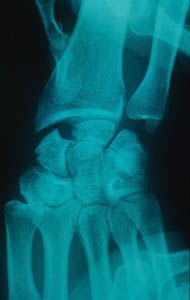

Mise au point Y a-t-il des indications à l'excision partielle du scaphoïde ? , Marc Garcia Elias Institut Kaplan, Chirurgie de la main et du membre supérieur Passeig de la Bonanova, 9, 2on 2a, 08022 Barcelone, Espagne , A. Lluch Institut Kaplan - Chirurgie de la main et du membre supérieur, Passeig de la Bonanova, 9, 2on 2a, 08022 Barcelone, Espagne N°127 - Octobre 2003 ● 16 min de lecture